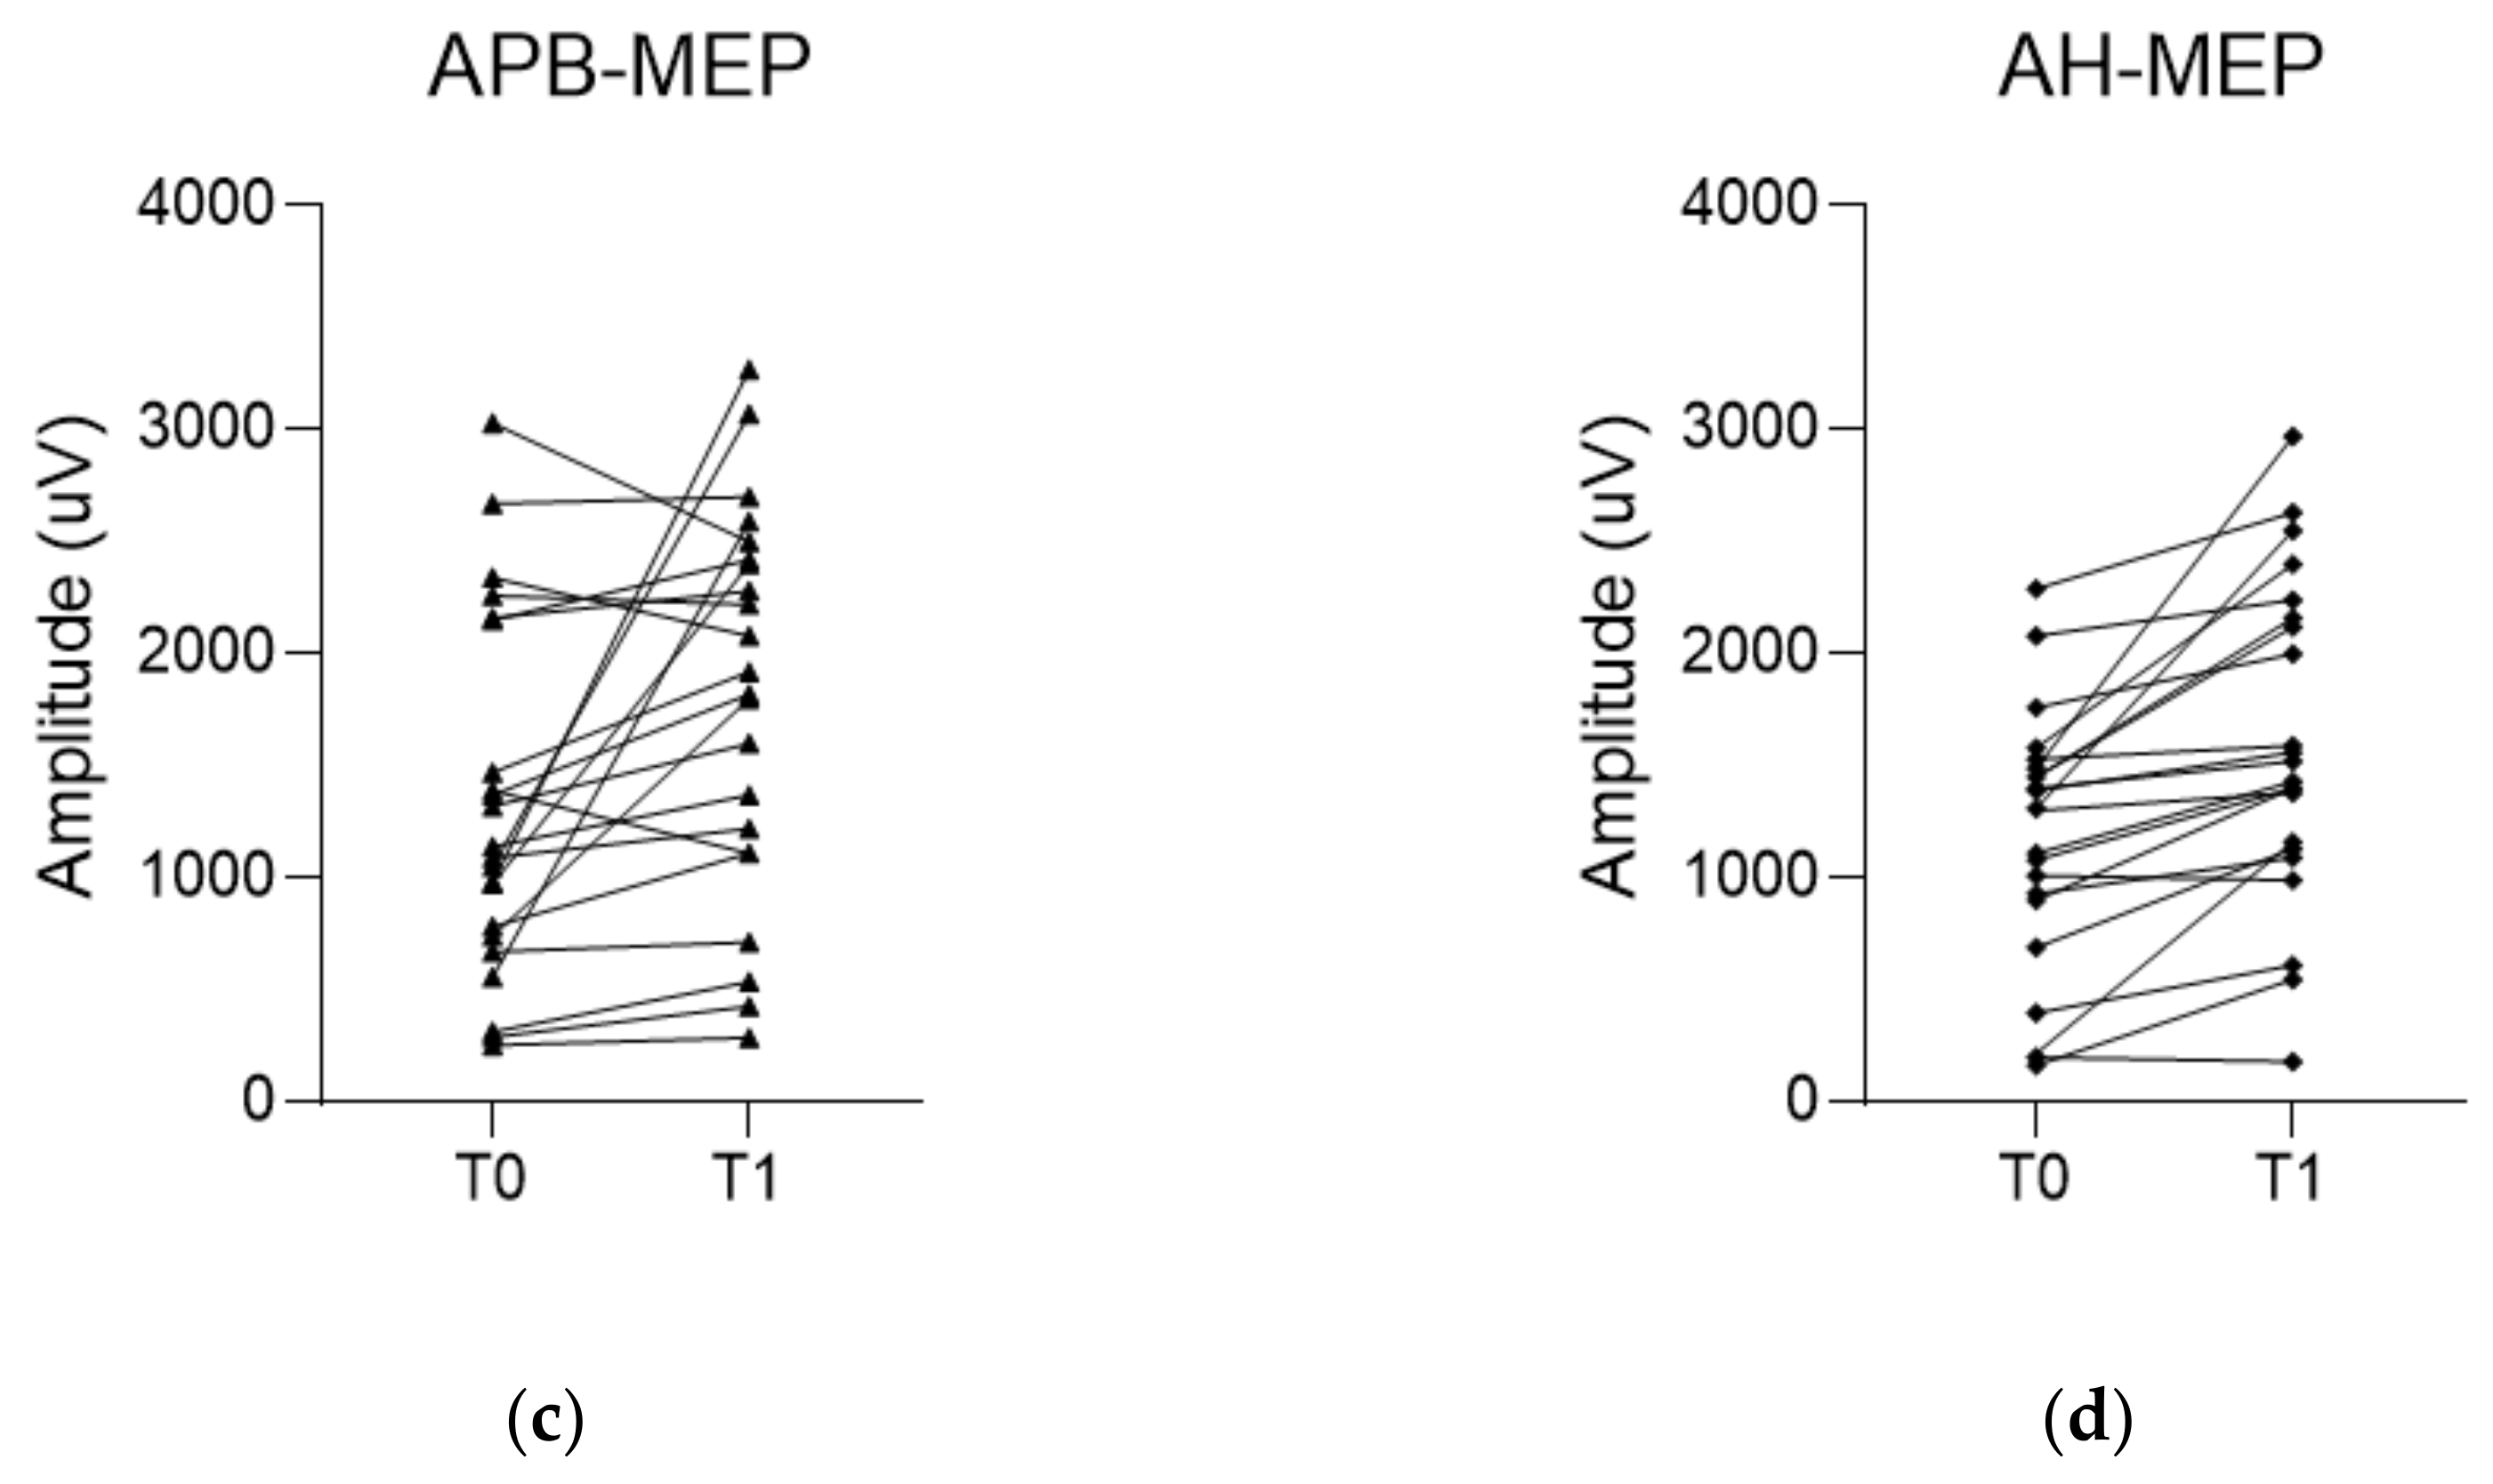

3.2. Comparison of EP Changes between the MB and MC Group

3.3. Changes in Examined Parameters and Their Correlations in the MB Group

| ΔMedian SSEP (%) | 13.8 (0.6, 41.3) | −4.3 (−19.8, 11.7) | 0.027 |

| ΔTibial SSEP (%) | 9.3 ± 26.8 | 1.5 ± 23.7 | 0.318 |

| ΔAPB-MEP (%) | 20.7 (5.6, 71.6) | 2.5 (−14.5, 12.9) | 0.006 |

| ΔAH-MEP (%) | 29.2 (8.6, 55.2) | 9.7 (−5.2, 28.2) | 0.015 |

| T0 a | T1 b | p-Value | |

|---|---|---|---|

| Median SSEP (µV) | 1.8 (1.0, 3.0) | 2.1 (1.4, 3.5) | 0.051 |

| Tibial SSEP (µV) | 0.9 (0.4, 1.6) | 1.0 (0.5, 1.9) | 0.604 |

| APB-MEP (µV) | 1318.9 ± 796.1 | 1793.2 ± 856.0 | 0.010 |

| AH-MEP (µV) | 1169.9 ± 576.2 | 1593.8 ± 721.6 | <0.001 |